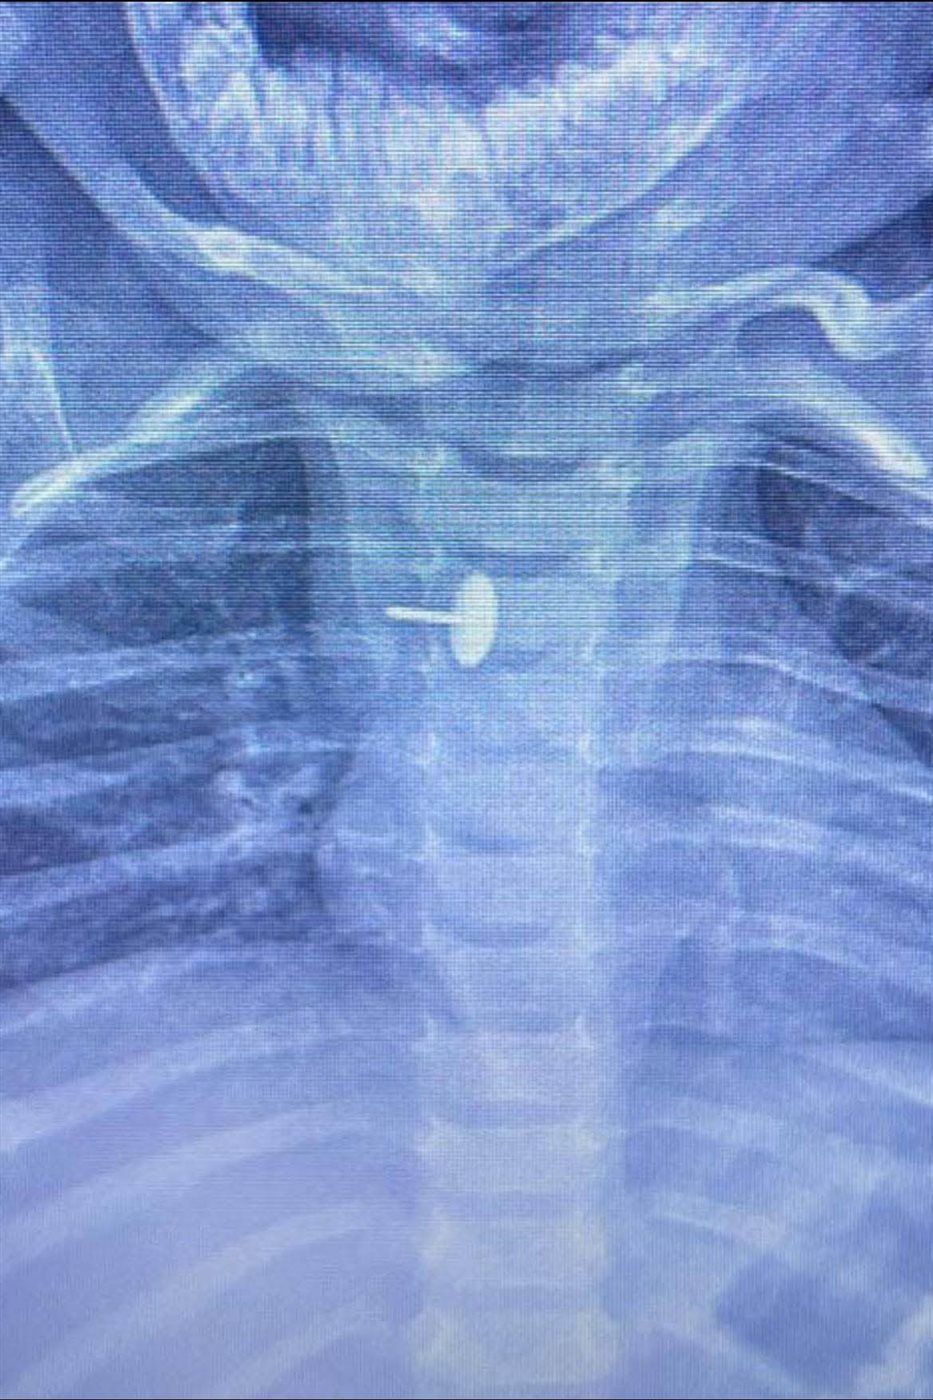

نجح فريق طبي بقسم جراحة الأطفال بمستشفى الأطفال التخصصي بمدينة بنها بالقليوبية، في إنقاذ حياة طفلة عمرها عام وسبعة أشهر، ابتلعت دبوس ضغط استقر داخل جدار المرئ لمدة تجاوزت ستة أشهر، ما تسبب في معاناتها المستمرة وصعوبة البلع طوال هذه الفترة.

قاد الفريق الطبي الدكتور محمد متولي رئيس قسم جراحة الأطفال، بمشاركة الأطباء وليد محمد وعبدالله أحمد أخصائيي جراحة الأطفال، والسيد الوصال نائب جراحة الأطفال، حيث أُجريت العملية باستخدام منظار الجهاز الهضمي وجهاز الأشعة سي-آرم ومنظار القصبة الهوائية، وسط إجراءات دقيقة ومتابعة مكثفة لضمان نجاح التدخل دون مضاعفات.

وأكد الفريق الطبي أن العملية تعد من الحالات النادرة والمعقدة نظرًا لطول مدة بقاء الجسم الغريب داخل المريء، مشيرين إلى أن نجاحها يمثل إنقاذًا حقيقيًا لحياة الطفلة التي كانت معرضة لمضاعفات خطيرة.